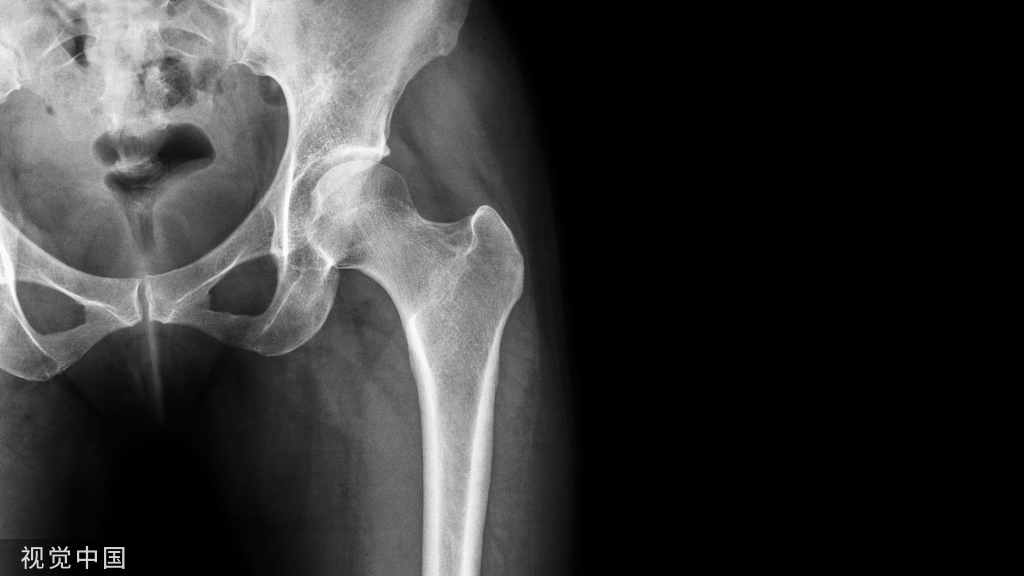

最新版指南:骨质疏松分级诊疗政策!

骨质疏松分级诊疗是对骨质疏松患者全程管理,早发现、早诊断、早治疗,全程管理的人群可分为4组:骨密度正常、骨量减少、骨质疏松、严重骨质疏松。对每组人群治疗制定相应的防治方案,畅通转诊,连续治疗。

骨质疏松分级诊疗目标